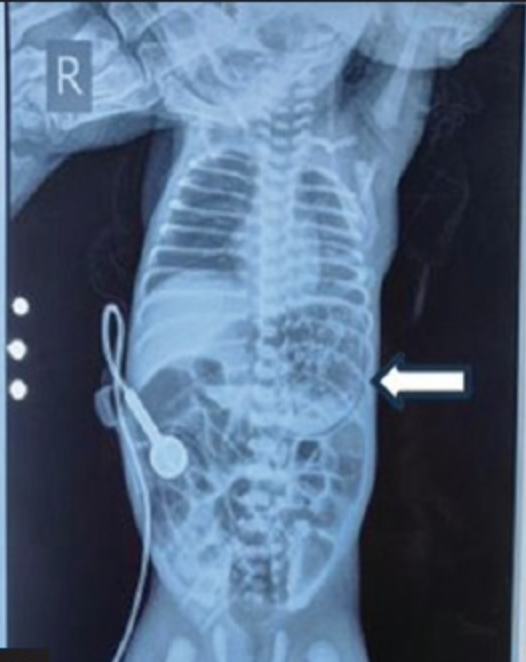

What are the diagnostic possibilities in this patient?

Female baby born by vaginal delivery at 34 weeks of gestation with a birth weight of 1.6 kg. Admitted to the NICU 3 hours after birth for prematurity and respiratory distress. Kept on CPAP, given surfactant. Started on enteral feeds of formula through orogastric tube. Was tolerating feeds well. At 50 hours of life developed tense abdominal distension. An erect abdominal radiograph showed the following: